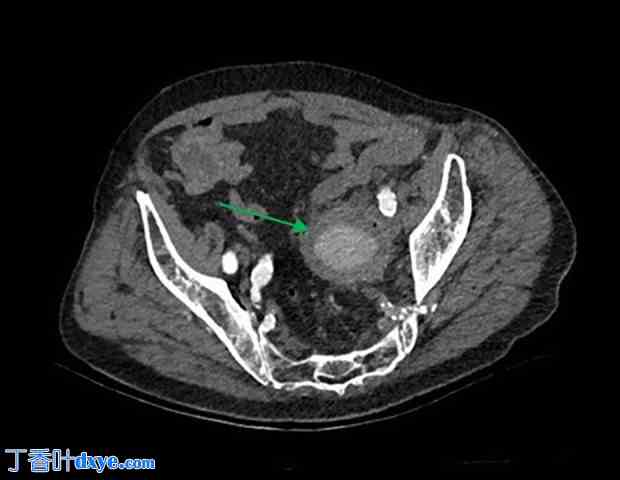

图 2.

介入治疗前血管造影图像显示髂内动脉瘤。